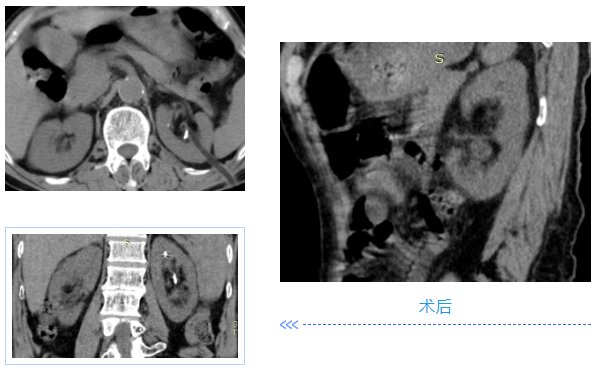

两名患者均为中年男性,入院检查发现肾内多发铸型结石,结石体积大、分布广,其中一例既往患肾行开放取石及经皮肾取石手术,盏颈狭窄伴有肾积水;另一例无明显积水,净石难度高。传统开放手术创伤大、恢复慢,单一微创技术难以彻底清除结石。针对患者病情,泌尿外科团队高度重视,多次组织病例讨论,结合患者身体状况与手术耐受度,最终制定“经皮肾镜+输尿管软镜”联合微创治疗方案。

在泌尿外科团队及麻醉科团队成员密切配合。患者取斜仰截石位,先通过输尿管软镜探查输尿管及肾盂肾盏情况,精准定位结石;随后在超声引导下建立经皮肾通道,置入经皮肾镜,利用钬激光碎石设备将复杂结石击碎成细小颗粒,部分结石因角度问题经皮肾镜无法够到,则通过软镜配合取石篮将结石拖入经皮肾通道口进行彻底清除。整个手术过程创伤小、出血少,术后患者恢复顺利,未出现相关并发症,现已康复出院。